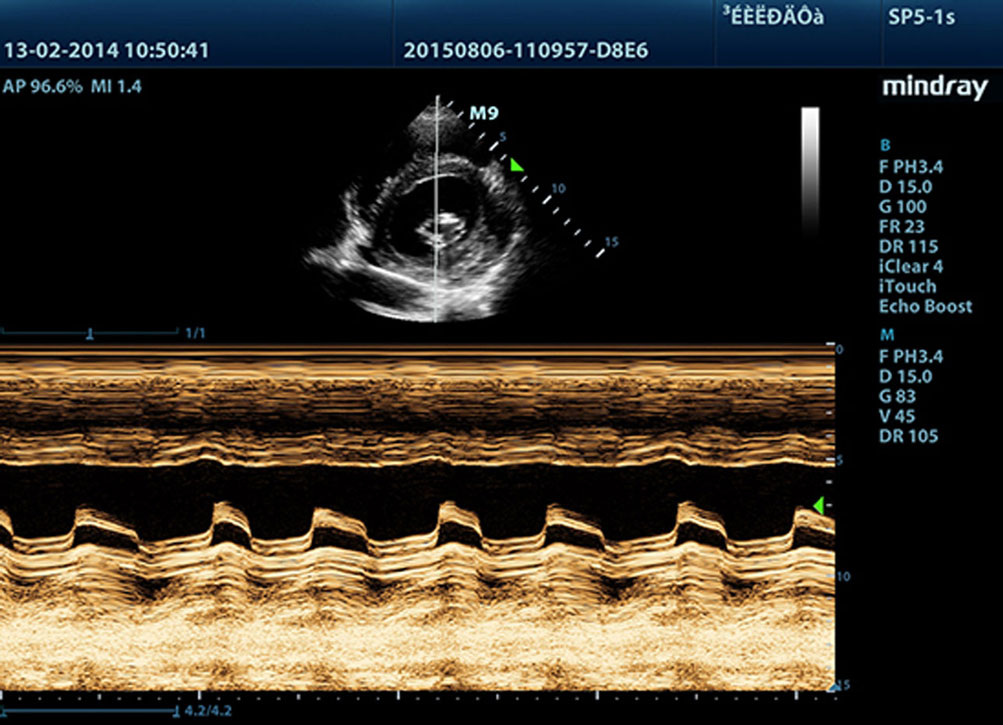

Dank Mindrays Ultraschallplattform der neuen Generation, mQuadro, hat das M9 den Branchenstandard auf ein bislang unbekanntes Niveau gehoben. Fortgeschrittene Signal├╝bertragung und ebensolche Empfangsprozessoren bieten hochsensitive, genaueste Echoerkennung. Innovative Schallkopftechnologie sorgt f├╝r bessere Penetration, h?here Aufl?sung und eine entsprechend einfachere Diagnose.

F├╝r sch?rfere Bilder sind alle mit dem M9 kompatiblen Sonden mit Mindrays einzigartiger 3T-Schallkopftechnologie ausgestattet. Das durch die Einkristalltechnologie verbesserte M9 bietet bessere Penetration und dynamischen Farbfluss, insbesondere bei der Untersuchung schwieriger Patientinnen oder Patienten.

iClear?

Verbesserte Bildqualit?t durch automatische Strukturerkennung

?

- Sch?rfere und durchg?ngige Kanten

- Glattes, einheitliches Gewebe

- Sauberere ?Kein-Echo-BereicheŌĆ£